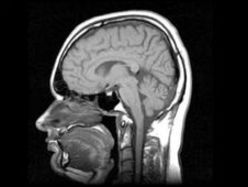

По его словам, препарат заставляет мозг взрослого человека вырабатывать новые стволовые клетки, которые в дальнейшем находят поврежденный орган и восстанавливают его. "У детей мозг активно вырабатывает стволовые клетки, потому что ребенок растет. И мозг взрослого человека способен их вырабатывать, только он не хочет этого делать — ему это не нужно. Наш препарат стимулирует выработку собственных стволовых клеток", — пояснил Артамонов.

По его словам, все операции со стволовыми клетками сейчас производятся вне организма человека, что несет на себе определенный риск, связанный с тем, что модифицированная, искусственно-размноженная клетка может начать взаимодействовать в неожиданном месте.

Клетки можно вводить, но это всегда является риском, потому что не очень понятно, где они дифференцируются. Они хоть и ваши, но размножены они вне вашего организма. Собственные стволовые клетки не могут не там дифференцироваться. Они находят поврежденный орган и начинают этот орган восстанавливать", — добавил Артамонов. Клинические испытания препарата продлятся полтора года, передает "Интерфакс".